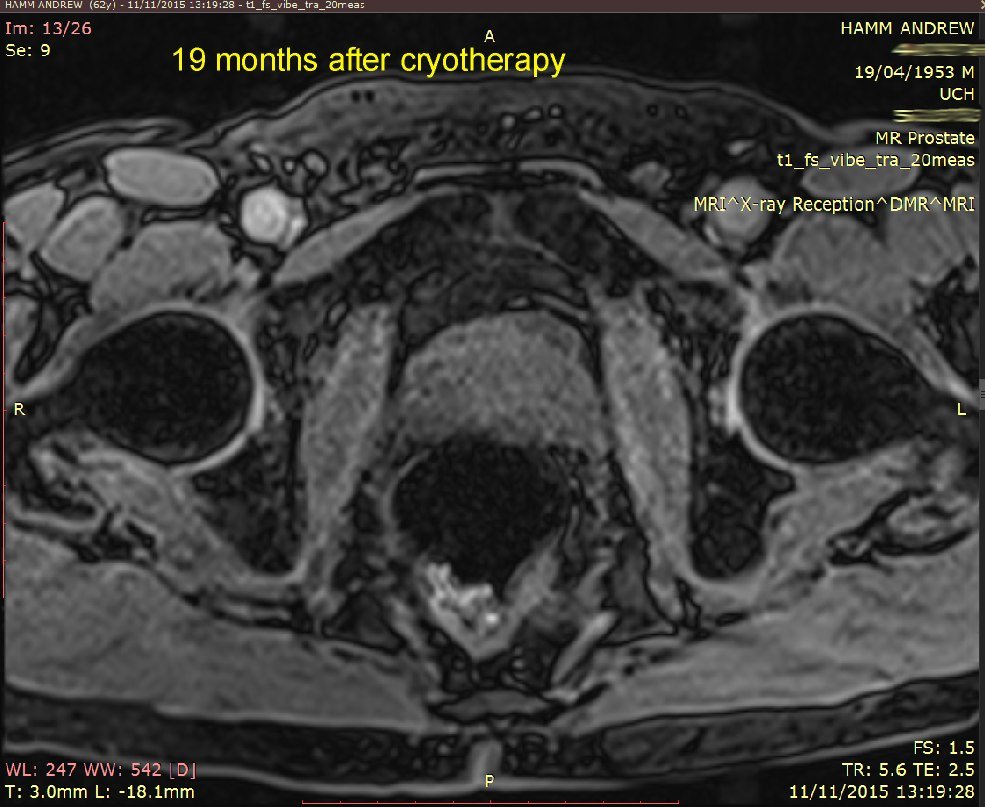

I've put 3 MRI images taken in November 2015. Compare these with my earlier ones below that, from 24 November 2014. Whilst not commenting specifically on these, the consultant said that the overall MRI had not revealed any significant (observable) prostate cancer.

18-day and 7-month MRI and PSA comparison - see image below.

Explanation: my prostate is roughly outlined in RED.

The original location of the tumour is roughly outlined in YELLOW on the 18-days image.

The ablated area is outlined in GREEN on the 18-days image.

These results show:

The ablated area has shrunk to (I presume) no volume at all.

My prostate volume has reduced by 5cc, which is pretty close to the 5cc volume that Emberton estimated would be ablated.

My PSA has rougly HALVED. The present PSA of 3.1 is within the range expected for a man of my age (61 years) who does not have significant prostate cancer.

My conclusion: Success! Cancer treated*.